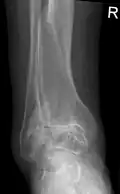

Diagnosis is made with reasonable certainty based on history and clinical examination.[52][53] X-rays may confirm the diagnosis. The typical changes seen on X-ray include: joint space narrowing, subchondral sclerosis (increased bone formation around the joint), subchondral cyst formation, and osteophytes.[54] Plain films may not correlate with the findings on physical examination or with the degree of pain.[55]

Severe osteoarthritis and osteopenia of the carpal joint and 1st carpometacarpal joint -

Primary osteoarthritis of the left knee. Note the osteophytes, narrowing of the joint space (arrow), and increased subchondral bone density (arrow). -